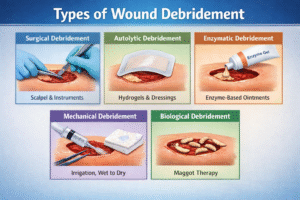

If you or someone in your family is living with a wound that refuses to heal — particularly a diabetic...